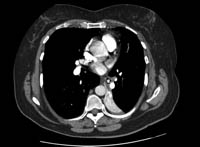

Chest x-ray

A chest x-ray should be obtained early in the evaluation of chronic cough.[38] Although it is not diagnostic of the most common causes, findings may quickly divert the evaluation to causes of greater gravity, such as structural lung diseases. These include lung cancer, pulmonary fibrosis, tuberculosis, bronchiectasis, pneumonia, aspiration, and sarcoidosis.[Figure caption and citation for the preceding image starts]: Chest x-ray showing hyperinflation in a patient with COPD. The hyperinflation is caused by the emphysema component of COPD, rather than the chronic bronchitis that underlies symptoms of coughFrom the personal collection of Dr M. A. Sharifabadand, SUNY at Stony Brook School of Medicine, Department of Pulmonary and Critical Care Medicine, Mineola, New York and Dr J. P. Parsons, The Ohio State University Medical Center, Columbus; used with permission [Citation ends].com.bmj.content.model.assessment.Caption@65a65855[Figure caption and citation for the preceding image starts]: Chest x-ray showing multiple miliary lung metastases (arrows). The primary tumour was a thyroid carcinomaE. Dick, Student BMJ. 2001;9:10-12 [Citation ends].com.bmj.content.model.assessment.Caption@25657fee[Figure caption and citation for the preceding image starts]: Chest x-ray showing left hilar carcinoma (arrow)From: E. Dick, Student BMJ. 2000;8:358-360 [Citation ends].com.bmj.content.model.assessment.Caption@567b9fef[Figure caption and citation for the preceding image starts]: Chest x-ray showing a cavitating right hilar carcinoma (arrow)E. Dick, Student BMJ. 2001;9:10-12 [Citation ends].com.bmj.content.model.assessment.Caption@3d6fa55[Figure caption and citation for the preceding image starts]: Chest x-ray in a patient with bronchogenic carcinoma showing a left-sided pleural effusionFrom: R. Thakkar, Student BMJ. 2001;9:458 [Citation ends].com.bmj.content.model.assessment.Caption@5b46acec[Figure caption and citation for the preceding image starts]: Chest x-ray showing interstitial fibrosis in a patient with amiodarone pulmonary toxicityFrom the personal collection of Dr A. Pataka and Professor P. Argyropoulou, Aristotle University, Thessaloniki, Greece; used with permission [Citation ends].com.bmj.content.model.assessment.Caption@2c3c94b0[Figure caption and citation for the preceding image starts]: Chest x-ray showing pulmonary tuberculosis with cavitationFrom the personal collection of Dr M. Narita, Department of Pulmonary and Critical Care Medicine, University of Washington [Citation ends].com.bmj.content.model.assessment.Caption@3dd7f84b[Figure caption and citation for the preceding image starts]: Chest x-ray showing multiple discrete nodules throughout both lungs (one of which is circled) in a patient with miliary tuberculosisE. Dick, Student BMJ. 2001;9:10-12 [Citation ends].com.bmj.content.model.assessment.Caption@23fa6365[Figure caption and citation for the preceding image starts]: Chest x-ray with lack of normal tapering producing a tram line in a patient with bronchiectasisFrom the personal collection of Dr S.M. Bhorade, University of Chicago Medical Center; used with permission [Citation ends].com.bmj.content.model.assessment.Caption@36b415f2[Figure caption and citation for the preceding image starts]: Chest x-ray with dilated and thickened airways in a patient with bronchiectasisFrom the personal collection of Dr S.M. Bhorade, University of Chicago Medical Center; used with permission [Citation ends].com.bmj.content.model.assessment.Caption@78e208fa[Figure caption and citation for the preceding image starts]: Chest x-ray showing increased opacification of the right perihilar region and superior segment of the right lower and upper lobes consistent with worsening aspiration pneumoniaFrom the personal collection of Dr R. Kanner, University of Utah School of Medicine [Citation ends].com.bmj.content.model.assessment.Caption@71be2c1f[Figure caption and citation for the preceding image starts]: Portable chest x-ray with bibasilar opacities, worse on the right than the left, in a patient with hospital-acquired pneumoniaFrom the personal collection of Dr F. W. Arnold, Division of Infectious Diseases, Department of Medicine, University of Louisville School of Medicine [Citation ends].com.bmj.content.model.assessment.Caption@2c704497[Figure caption and citation for the preceding image starts]: Chest x-ray showing early ill-defined opacities of the right upper lobe above the minor fissure consistent with early changes of aspiration pneumoniaFrom the personal collection of Dr R. Kanner, University of Utah School of Medicine [Citation ends].com.bmj.content.model.assessment.Caption@23fa54d0[Figure caption and citation for the preceding image starts]: A. Portable upright chest x-ray before aspiration; B. Chest x-ray 1 hour after aspiration, showing bilateral diffuse alveolar infiltrates, worse at the bases on the right sideFrom the personal collection of Dr S. Murgu and Dr H. Colt, University of California at Irvine Medical Center [Citation ends].com.bmj.content.model.assessment.Caption@7860be3a[Figure caption and citation for the preceding image starts]: Chest x-ray showing bilateral hilar adenopathy in a patient with sarcoidosisFrom the personal collection of Dr M.P. Muthiah, Division of Pulmonary and Critical Care and Sleep Medicine, University of Tennessee [Citation ends].com.bmj.content.model.assessment.Caption@31e94b4e